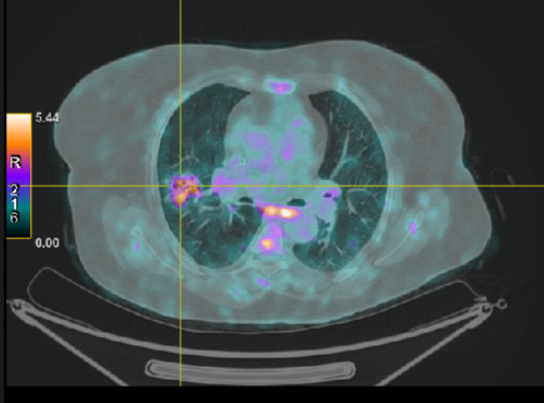

A post-chemotherapy PET scan showed the disappearance of the pulmonary lesion and the persistence of lymphadenopathies that were of sarcoidosis origin.

Fig 2

Figure 2